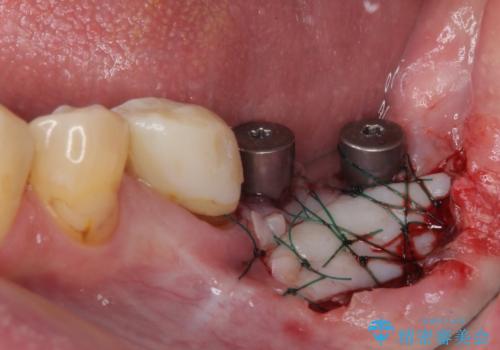

並行して左下にはインプラントを埋入し、上顎臼歯部の気になる部分も根管治療などを進めて行き、矯正治療を終えると同時に補綴治療を行うこととしました。

痛みのある奥歯は必要に応じて根管治療を行い、左下インプラントは角化歯肉の移植により清掃性を向上させ、気になっていた部分をしっかりと改善させることができました。